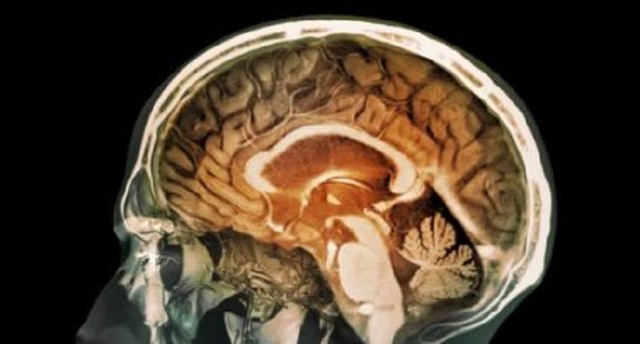

Theo một nghiên cứu mới đây, các phân tử gây ô nhiễm đã được phát hiện trong các mẫu mô não.

Các nghiên cứu hiện nay đã cung cấp bằng chứng đầu tiên về việc các phân tử ô-xít sắt từ bắt nguồn từ ô nhiễm có thể tìm được đường riêng để xâm nhập vào não.

“Đó là một phát hiện gây sốc khủng khiếp. Khi nghiên cứu các mô não và nhìn thấy các phân tử này nằm phân tán giữa các tế bào, và khi thực hiện một chiết xuất từ tính thì có hàng triệu phân tử - hàng triệu hạt trong chỉ 1gram mô não – nghĩa là sẽ có hàng triệu rủi ro mô não bị tổn thương”. Tổn thương tế bào do ô-xy hóa là một trong những đặc điểm đầu tiên của bệnh Alzhermer, và đây là lý do tại sao sự hiện diện của ô-xít sắt từ lại có nguy cơ đáng kể như vậy, vì nó có các phản ứng sinh học như vậy.